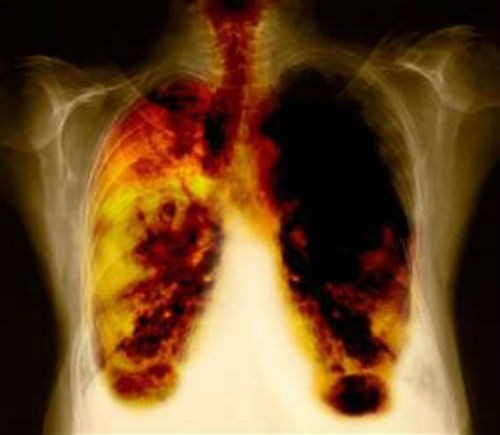

Hình ảnh ung thư phổi do hít khói bụi, bồ hóng. |

Bác sĩ Đặng Thế Căn – Nguyên Giám đốc Bệnh viện K Hà Nội cho biết, có trường hợp bệnh nhân phổi bị đen do hít phải khí than quá nhiều. Một số lại bị nhiễm bụi phổi Silic từ bụi đá. Ô nhiễm khói bụi khiến bệnh tật ngày càng nhiều hơn, trong khi đó tình trạng hút thuốc lá, sử dụng than mỏ trong sinh hoạt vẫn không giảm.